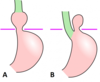

- Types of hiatus hernia

- structures involved

- how common they are (%)

Hiatus hernia

A. Sliding - 80%: gastro-oesophageal junction, cardia of the stomach move through diaphragmatic hiatus into the thorax

B. Rolling (para-oesophageal) - 20%: fundus of the stomach moves up and the stomach protrudes next to the oesophagus -> ‘bubble’ of the stomach in the thorax (peritoneal sac)